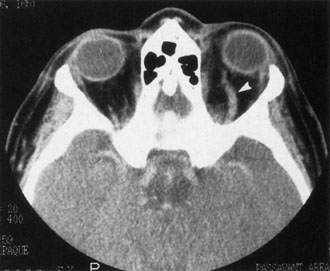

Contrast-enhanced CT of the orbits with direct and coronal cuts is the radiologic study of choice for these patients.45 A well-demarcated, encapsulated oval or rounded mass is revealed, which is typically intraconal in the lateral part of the middle third of the orbit (Fig. 5) but occasionally may extend to the extraconal space.42 Septa within the tumor may be apparent on high-resolution CT. The posterior pole of the globe frequently is indented by the rounded anterior margin of the tumor.42 The optic nerve typically is displaced rather than surrounded by the tumor. Subtle outward bowing of the lateral orbital wall or increase in orbital size may be present, consistent with a long-standing, slowly growing mass lesion.10,42 Enhancement with intravenous contrast occurs and may be homogeneous or inhomogeneous.10,45 Rarely, cavernous hemangiomas may occur as an intraosseous tumor within the orbital or facial bones.42,53–55 Although usually an isolated intraorbital lesion, multiple lesions in one orbit occurred in 8 of 164 (5%) patients of three combined large studies,10,42,45 and bilateral multiple cavernous hemangiomas also have been described.56 In contrast to patients with venous flow malformations in which phleboliths are common, phleboliths are rare in cavernous hemangiomas. Three large studies comprising 164 patients with cavernous hemangioma all reported that no calcification was detected within the tumor.10,42,45If the diagnosis is still unclear or if better definition of details and localization of the lesion is required, then MRI should be performed. Magnetic resonance imaging demonstrates nonspecific characteristics of a lesion isointense to muscle and gray matter on T1-weighted images and hyperintense on T2-weighted images (Fig. 6).57 The lesions show initial central patchy enhancement, which fills up homogeneously within 20 to 60 minutes.58 If ultrasonography is performed, B-scan ultrasonography shows a well-circumscribed mass with a sharply defined anterior acoustic border.23 A-scan ultrasonography shows high reflectivity of the echo signals resulting from the multiple blood-filled vascular channels, regular internal structure with a higher anterior and posterior spike marking the capsule, and moderate sound attenuation (angle of decrease of the echo spike within the lesion).24 Arteriography is not indicated.

Fig. 5. Cavernous hemangioma. Contrast-enhanced axial computed tomography scan shows a well-demarcated, oval intraconal mass in the lateral part of the middle third of the orbit. Note the enhancement within the lesion, which in this instance is inhomogeneous, but can also be homogeneous.

Fig. 6. Cavernous hemangioma. Axial magnetic resonance imaging demonstrates a well-defined, homogeneous intraconal mass that is isointense to muscle and gray matter on T1-weighted image (A), and hyperintense on T2-weighted image (B). Note the displacement of the optic nerve and indented posterior globe.